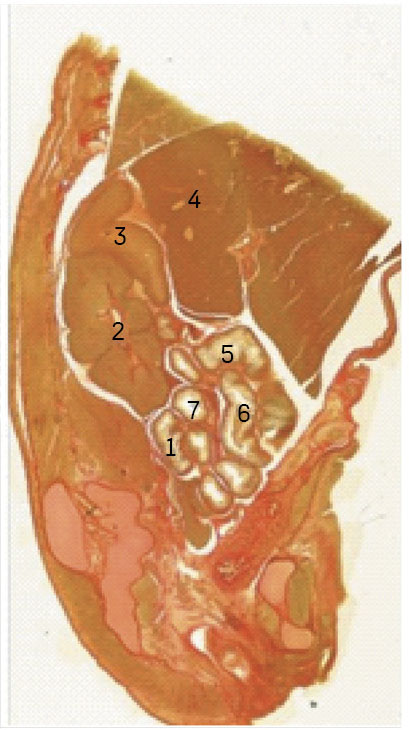

Histotopograms of different section planes (sagittal, frontal, and horizontal) allow for clear detailing of the anatomical features of the cecum and vermiform appendix in the human fetus (Figure 5).

Figure 5. Anatomy of the ileocecal angle of the human fetus. Photo histotopogram for MBS-10 (sagittal section). Van Gieson staining. 2×14 magnification. Protocol No. 200, fetal age: 22 weeks, sex: female. 1 – ileocecal angle; 2 – right kidney; 3 – right adrenal gland; 4 – liver; 5 – transverse colon; 6 – descending colon; 7 – loop of the small intestine.

The weakly folded wall, smooth mucosa of the cecum, and occasional semilunar folds are identified, along with the protruding ileocecal valve. The wall thickness can be measured both at the dome of the cecum and at the Bauhin’s valve.